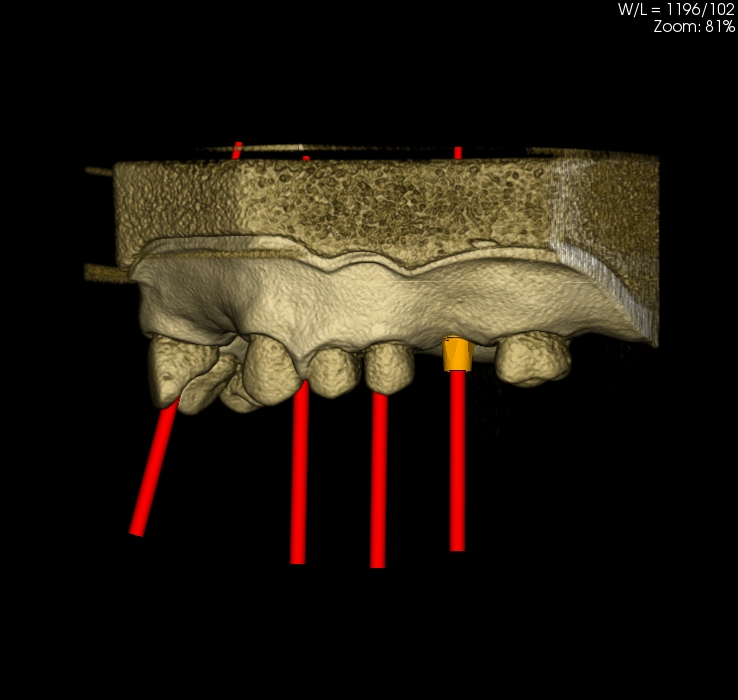

Oferujemy również szablony chirurgiczne przeznaczone do szkoleń z implantacji. Umożliwiają planowanie leczenia implantologicznego i przeprowadzenie szkoleń z wykorzystaniem plików CT, STL oraz druku 3D. Oferujemy nasze modele do szkoleń implantologicznych wraz z plikami DICOM i STL.

Pliki do wykonania szablonów można pobrać z naszej strony internetowej. Możemy je również dostarczyć wraz z modelami. Pliki te dostępne są dla modeli 10-1030, 10-3040, 10-3050, 10-5070,

Istnieje również możliwość dostarczenia szablomów w oparciu o pliki i informację o planowanej procedurze implantologicznej.

Model szczęki z zębami w pozycjach 11, 13, 14, 23, 24, 25 i 27, brakiem zębów w wygojonych pozycjach 21, 22, 26, 15, 16. Umieszczenie dwóch zagłębień imitujących niezagojone zębodoły w pozycjach 17 i 12 umożliwia ćwiczenie implantacji wczesnej i natychmiastowej. Wykonany jest z jednorodnego materiału o właściwościach zbliżonych do kości ludzkiej.  Model pokryty jest śluzówką, którą można nacinać i zszywać. Znakomicie nadający się także do  nauki implantacji odroczonej i planowania leczenia poekstrakcyjnego. Umożliwia również przedstawienie problemów związanych z prawidłowym umieszczeniem implantów pomiędzy koronami sąsiadujących zębów. Model można stosować w najbardziej popularnych na rynku fantomach jak i głowie fantomowej PROMEDICU 11-1000 jak również samodzielnie bez niego.

Poniżej znajduje się przycisk umożliwiający ściągnięcie pliku STL przeznaczonego do wykonanie szablonu do szkoleń implantacyjnych z użyciem modelu.

Numer katalogowy 10-5070